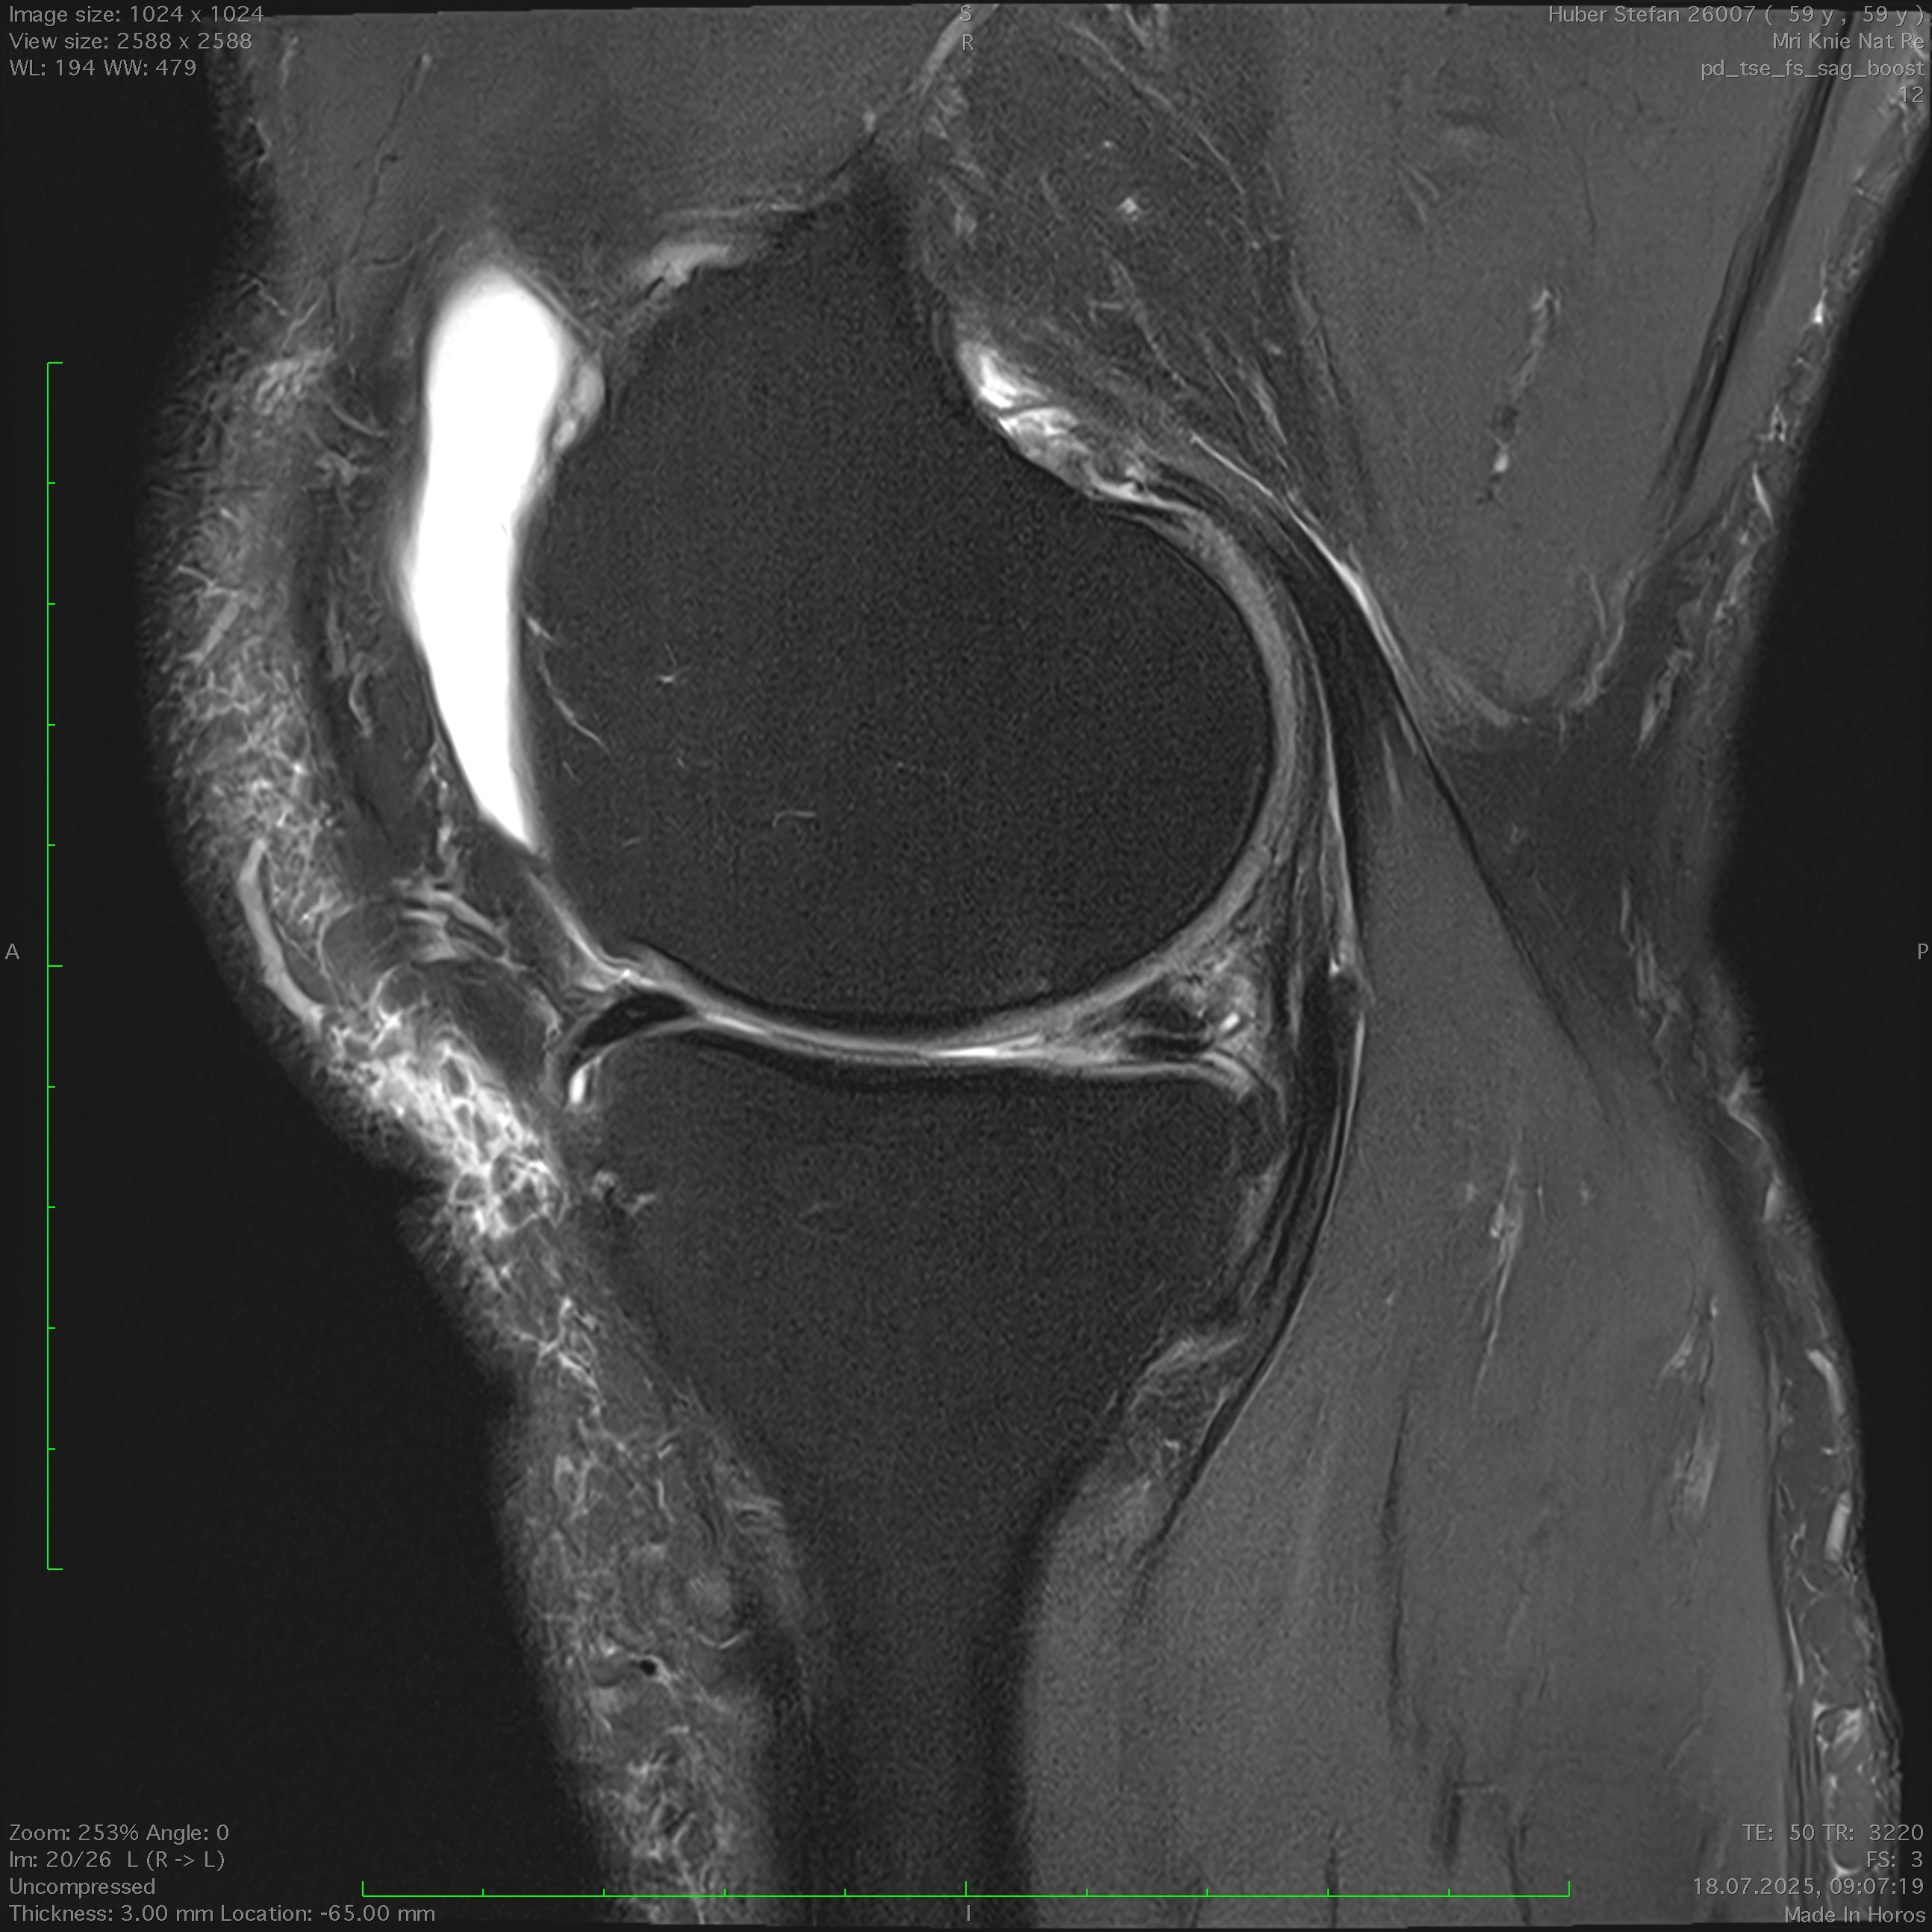

MRI: Bestätigung des Risses und Beurteilung der Rissform und -zone